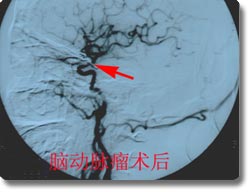

开展了脑动脉瘤、脑血管畸形、颈内动脉海绵窦瘘、脊髓血管畸形的神经介入治疗和恶性肿瘤的次选择性化疗,尤其是对巨大动脉瘤的栓塞成功率达到国内领先水平。同时开展了脑动脉瘤、动静脉畸形、高血压脑出血的手术治疗和血管闭塞性疾病的颅内外搭桥手术、颈内动脉内膜切除术、急性栓塞的溶栓治疗术、血管内支架放置手术,颅内动脉瘤电解可脱性螺旋圈(CDC)治疗,先后收治病人4000余例,积累了丰富的经验,为脑血管狭窄、脑供血不足及脑血栓病人的康复提供了有力保证。介入治疗具有不出血、无感染、损伤小、风险小、恢复快的优点,是脑血管疾病病人的理想选择。2003年,与北京宣武医院强强联合成立了北京市脑血管病中心重庆分中心。2005年成功地承办了第七届全国神经外科血管内治疗研讨会,受到了与会专家的一致赞誉。 |